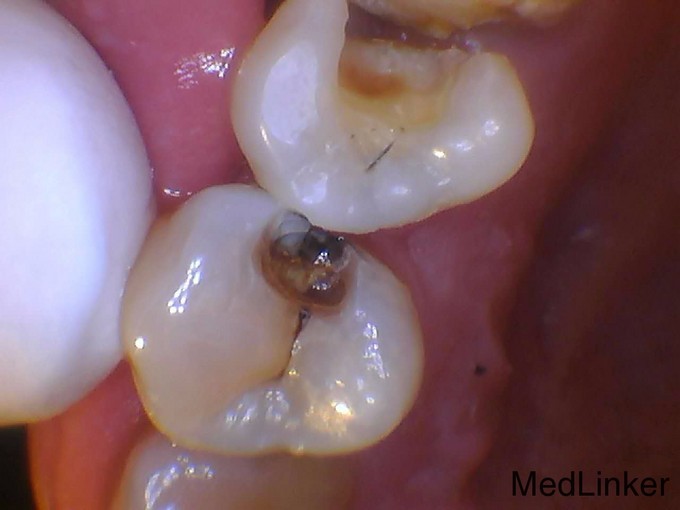

1113牙体龋坏的嵌体修复光7

左上后牙有牙洞,要求治疗